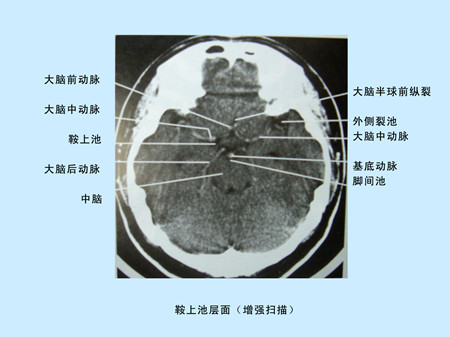

CT(Computed Tomography)是電子計(jì)算機(jī)X射線斷層掃描技術(shù)簡(jiǎn)稱。CT的工作程序是這樣的:它根據(jù)人體不同組織對(duì)X線的吸收與透過(guò)率的不同,將測(cè)量所獲取的數(shù)據(jù)輸入電子計(jì)算機(jī),電子計(jì)算機(jī)對(duì)數(shù)據(jù)進(jìn)行處理后,攝下人體被檢查部位的斷面或立體的圖像,可發(fā)現(xiàn)體內(nèi)任何部位的細(xì)小病變。CT圖像是重建圖像。

CT由于它的特殊價(jià)值,已廣泛應(yīng)用于臨床。但CT設(shè)備比較昂貴,檢查費(fèi)用偏高,某些部位的檢查,價(jià)值,尤其是定性,還有一定限度,所以不宜將CT檢查視為常規(guī)手段,應(yīng)在了解其優(yōu)勢(shì)的基礎(chǔ)上,合理的。在頭部檢查中,CT可用于腦出血,腦梗塞,動(dòng)脈瘤,血管畸形,各種腫瘤,外傷,骨折,先天畸形等方面的。

CT平掃及增強(qiáng)掃描腦組織圖像顯示 超聲經(jīng)顱多普勒檢測(cè)時(shí)顯示圖像